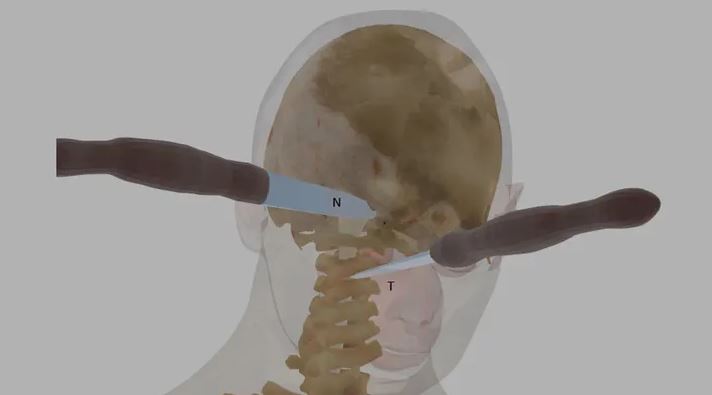

根據外媒《Fox News》的報導,2011年,美國費城一名27歲的女教師艾倫 (Ellen Greenberg) 被發現陳屍在公寓,她渾身是傷、身中20刀,有一半的刀傷都在後腦勺,甚至胸口還插著一把10英吋 (25.4公分) 的刀子。第一時間打電話報警的未婚夫山姆 (Sam Goldberg) 成了頭號嫌疑犯。

儘管現場血跡斑斑,艾倫的屍骨豊也有被移動過的痕跡,調查人員仍表示沒有在現場發現掙扎或打鬥證據,室內也沒有外力入侵的跡象,因此排除了謀杀殳的可能。起初,法醫根據艾倫的傷勢判定為他杀殳,但在警察部門介入商討後,死因竟改成了「自//殺」,山姆也因此全身而退。

這樣的結果讓艾倫的家屬完全無法接受,認為有10刀是刺進後腦怎麼可能是「自//殺」,甚至請了第三方驗屍專家鑑定,發現有2刀還是在心跳停止後刺入的。此外,山姆的供詞也起人疑竇,他聲稱自己是破壞門鎖才得以進屋,但犯罪現場的門鎖完好無缺。艾倫的爸媽決定訴諸媒體並向法院遞案,要求司法單位重啟調查女兒的案件。